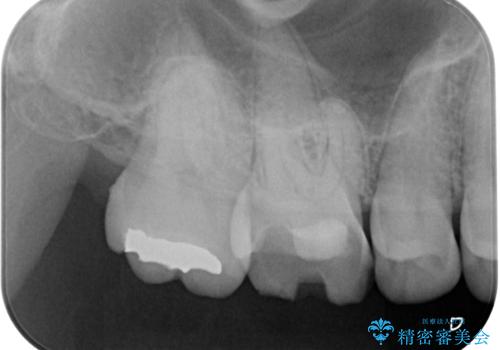

CT を撮影して確認したところ、歯肉より4ミリ程度深い場所で破折していました。患者様と相談して、外科的な介入はせずに被せもののみでの治療を行うこととしました。

拡大鏡視野下で詰め物と虫歯の除去を行い、詰め物の範囲が大きかったためオールセラミッククラウンに適した形に整えました。